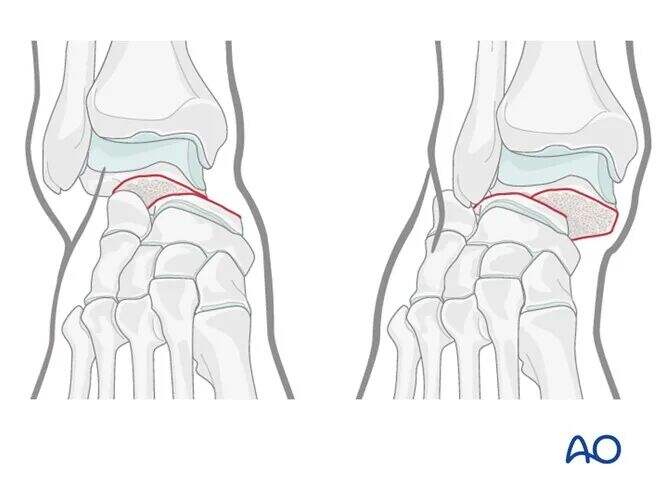

Ti vijaki ne morajo biti postavljeni vzporedno, saj se njihovi mehanizmi razlikujejo: lateralni vijak zagotavlja kompresijo, medtem ko medialni vijak služi le za pozicijsko fiksacijo.

Ilustracija prikazuje stabilno fiksacijo zloma tipa Hawkins II. Obravnavajte nevzporedno postavitev vijakov: kompresijski vijak lateralno in pozicijski vijak medialno.